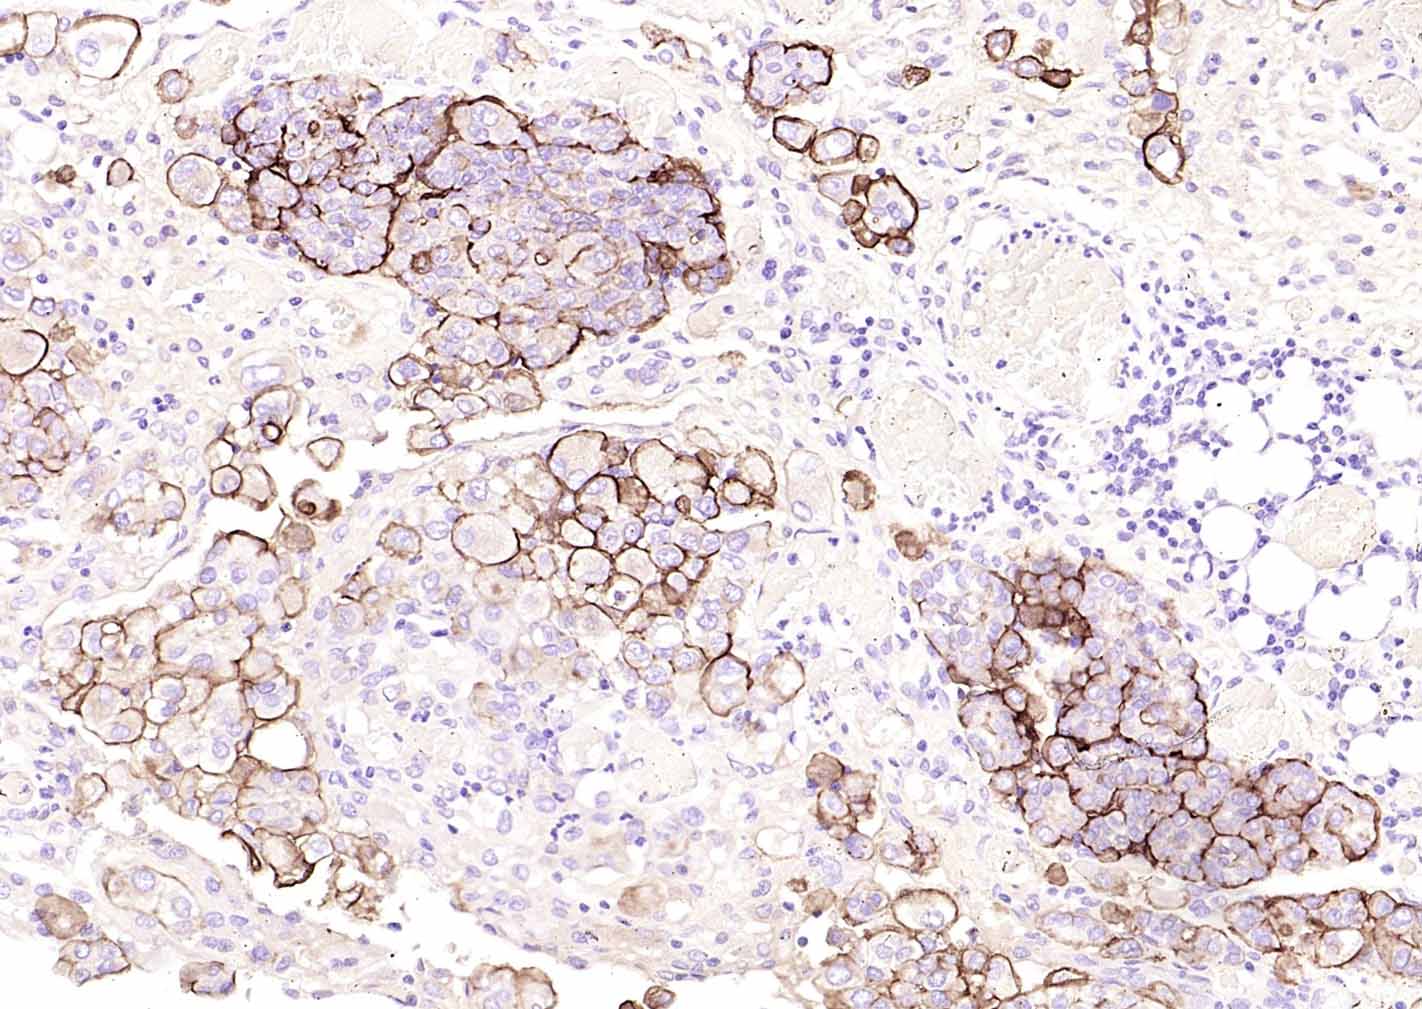

间皮素(mesothelin, MSLN)是一种相对分子量:64kDa的细胞表面糖蛋白, 在间皮瘤、 卵巢癌、 胰腺癌等恶性肿瘤中有较高的表达。主要用于恶性肿瘤的研究。

Mesothelin(MSLN)may play a role in cell adhesion and cell shape dynamics; human homolog highly expressed in renal cell carcinoma. malignant tumors, such as a skin lump, ovary cancer and the pancreas cancer...etc..Mainly used for the research of the malignant tumor.

IHC-PHuman1:100-500

Expressed in lung. Expressed at low levels in heart, placenta and kidney. Expressed in mesothelial cells. Highly expressed in mesotheliomas, ovarian cancers, and some squamous cell carcinomas (at protein level).